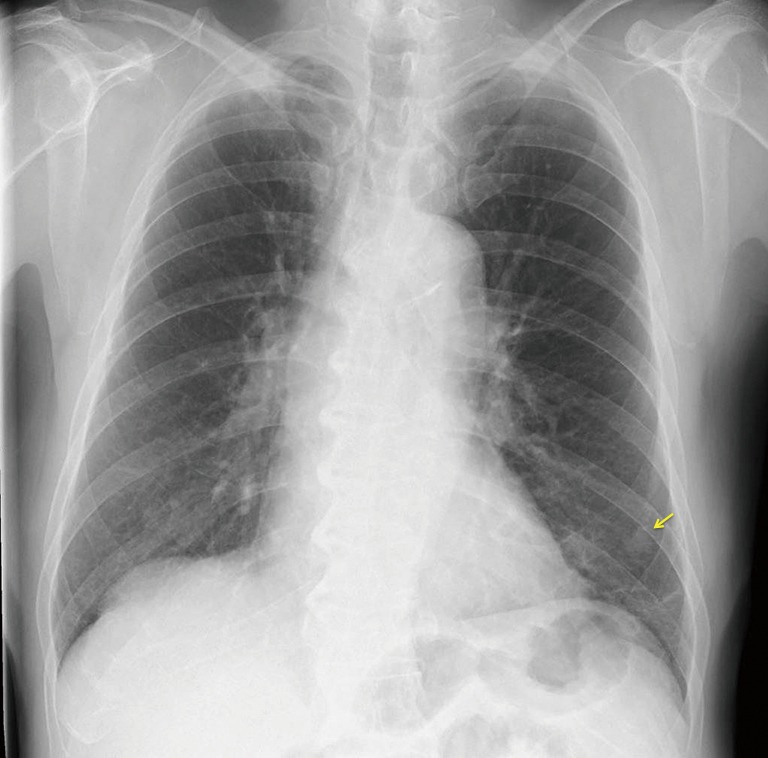

A 68-year-old male patient visited our center because of abnormalities found on chest radiography (Figure 1). He was a heavy smoker, smoking 1 pack a day for 40 years. His medical history included sarcoidosis, which had occurred 3 years previously and required regular visits at another hospital. Blood examination showed elevated levels of certain tumor markers, e.g., carcinoembryonic antigen (CEA) 34.3 ng/mL and sialyl Lewis X-1 (SLX) 170 U/mL.

Figure 1.

Chest X-ray at presentation showing a nodular shadow in the left lower lung field. The arrow indicates the lesion.